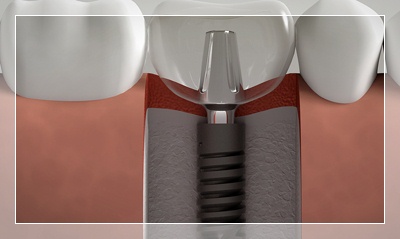

İmplantoloji

Eksik dişleriniz için en modern ve kalıcı çözüm. Titanyum implantlarla doğal diş görünümü ve fonksiyonu. Çekmeköy'de deneyimli kadromuzla implant tedavisi.